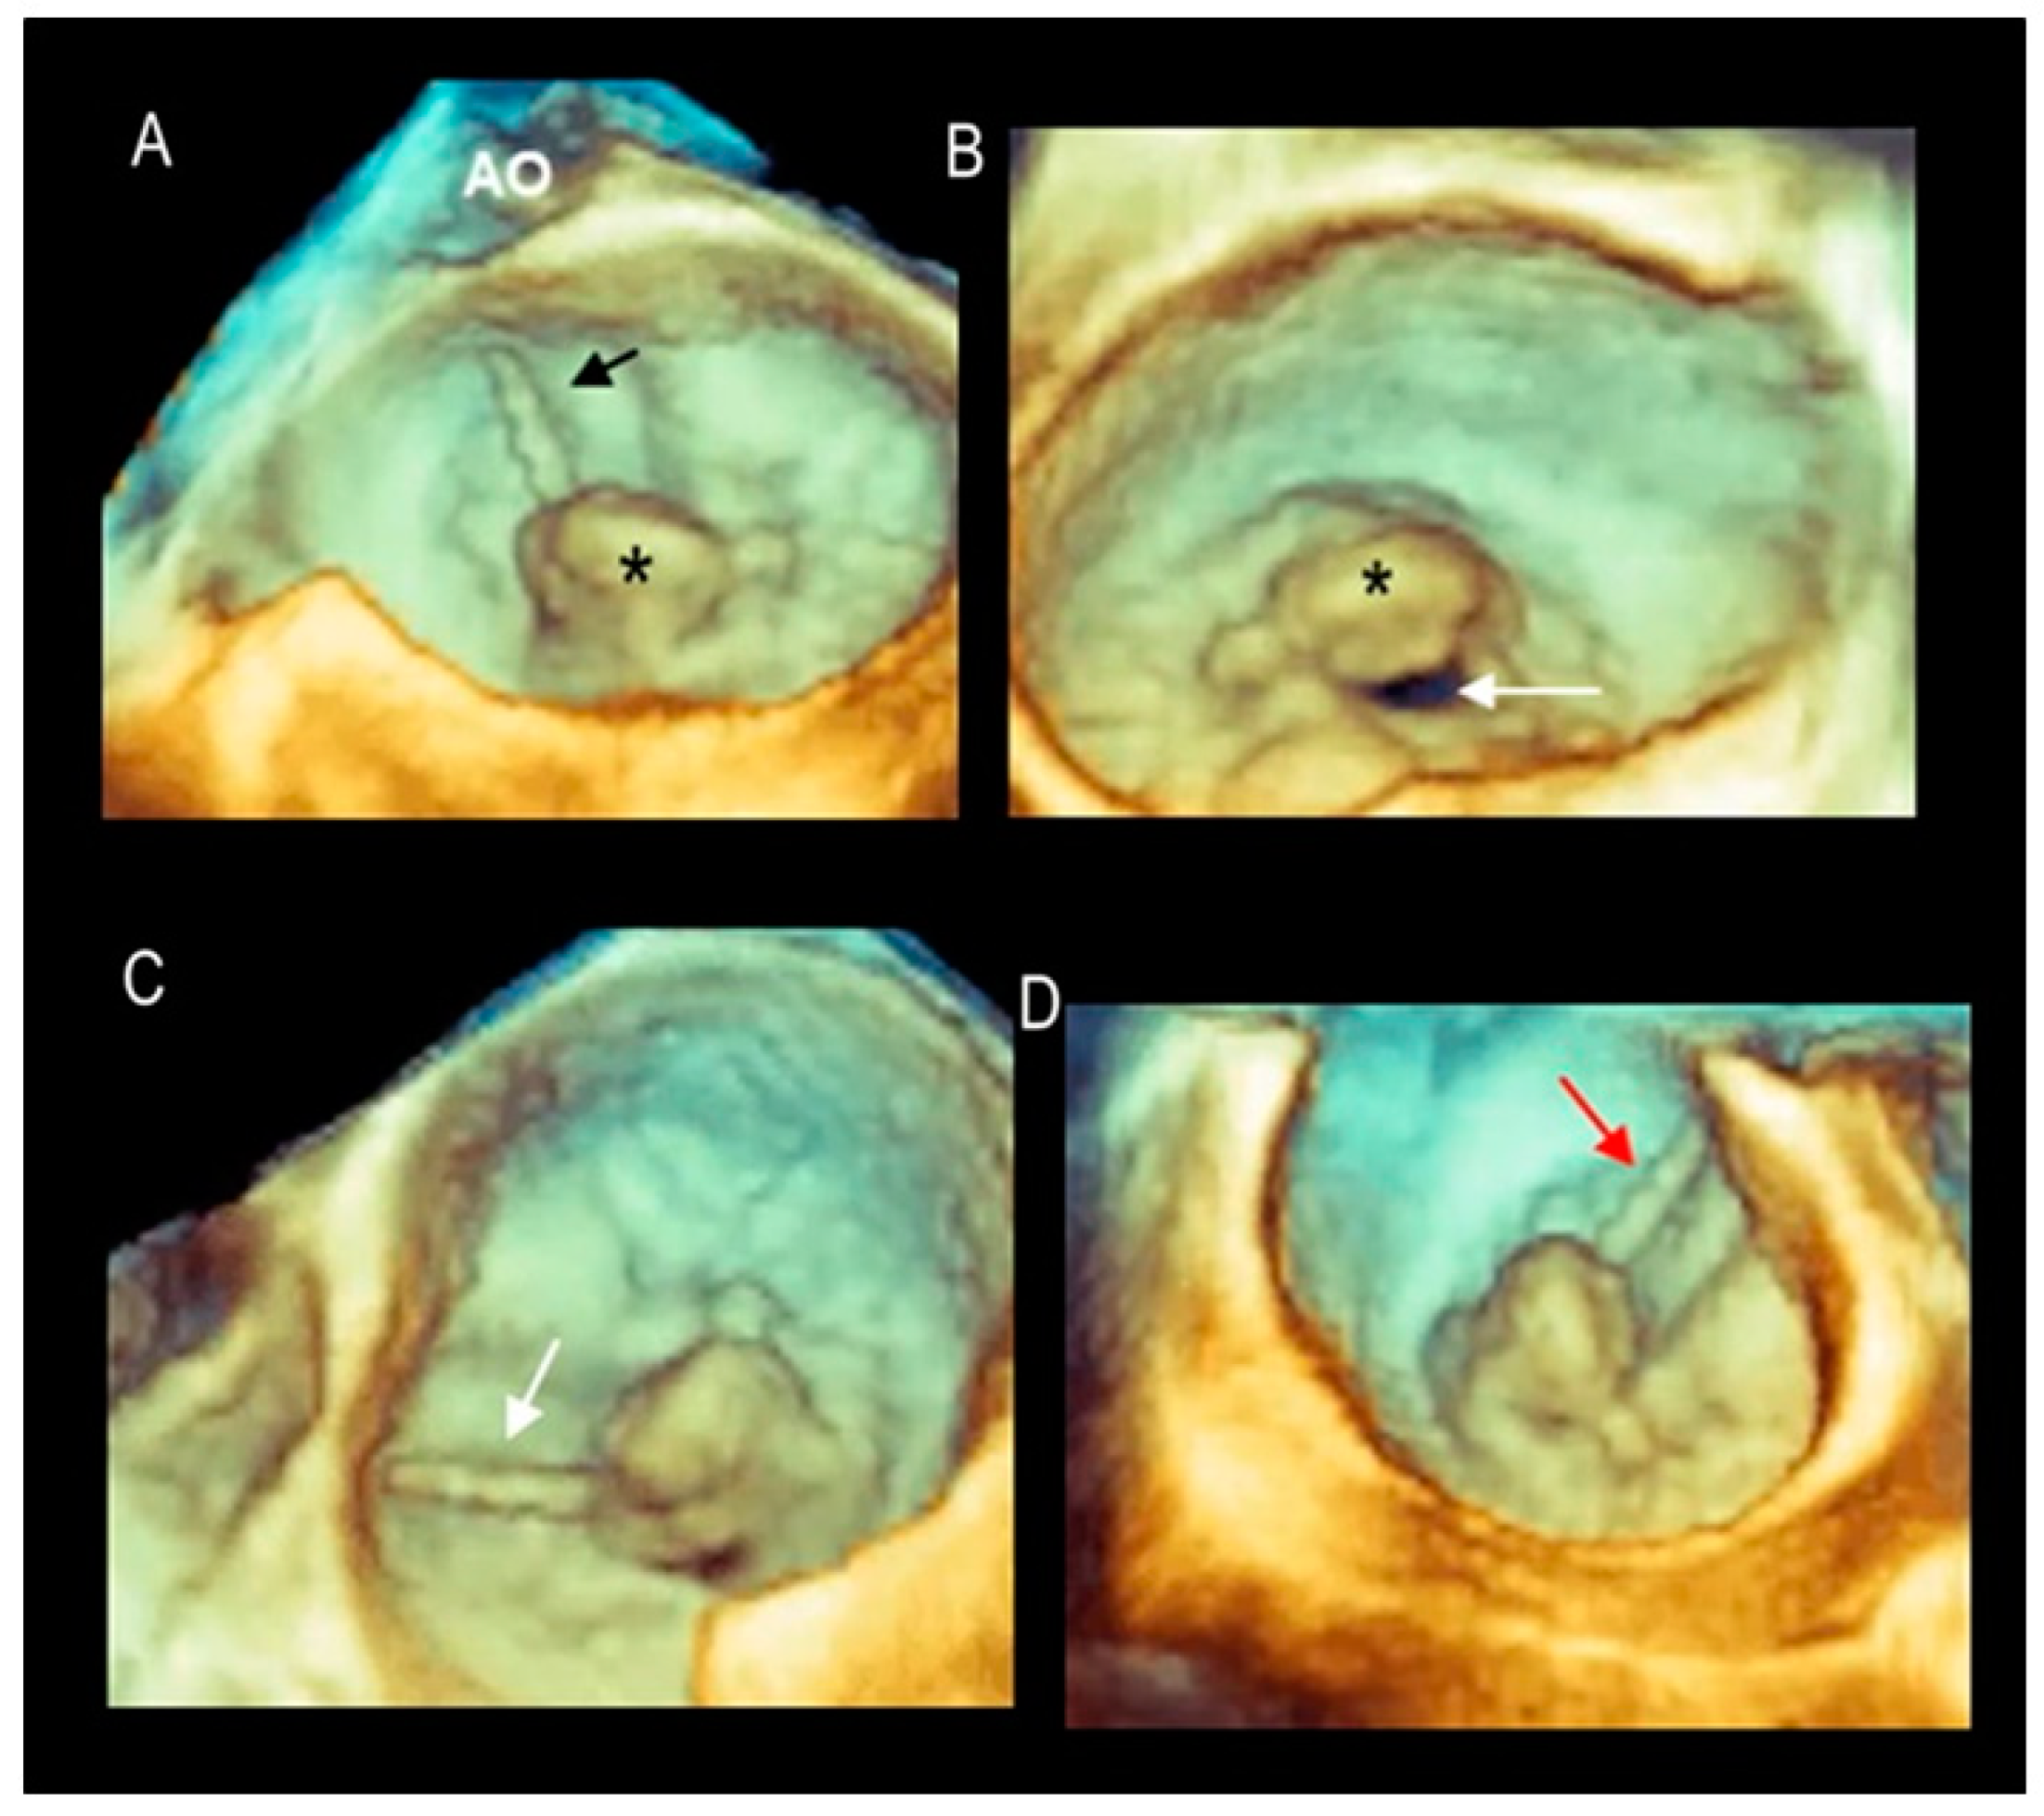

2.2. Scenario # 2

Phenotypes of DMVR

| Phenotype | Description | Image |

|---|---|---|

| Fibroelastic deficiency | This phenotype is characterized by a deficient production of collagen, elastin, and proteoglycans. Leaflets preserve their own three-layer arrangement, but upon surgical inspection, they appear fragile and translucent. The etiology of connective tissue deficiency in FED is unknown, but it has been suggested that it may be the result of an accelerated ageing process. The cause of regurgitation is the rupture of one or more primary chordae tendineae, which usually involves a single scallop. The figure shows a small P2 prolapse in an otherwise apparently normal MV. |  |

| Fibroelastic deficiency plus | This phenotype is characterized by a single scallop prolapse, but the involved scallop is redundant and affected by myxomatous degeneration. The remaining scallops are normal. Qualitative histological lesions in the prolapsed tissue of FED plus are similar to those of Barlow’s disease. It has been suggested that FED plus may be considered a sort of worsening stage of FED, leading to the hypothesis that the myxomatous changes could also be secondary to jet lesions. The figure shows a large P2 prolapse with ruptured chordae tendineae (arrows). |  |

| Forme fruste | In this phenotype, the entire posterior leaflet is redundant and is affected by myxomatous degeneration, while the anterior leaflet is macroscopically and histologically normal. It can be speculated that this phenotype is an incomplete form of Barlow’s disease. The figure shows multiple prolapses (asterisks) of the posterior leaflet. |  |

| Barlow’s disease | Barlow’s disease is the result of an abnormal accumulation of myxomatous substances (mainly proteoglycans) in the spongiosa layer, and a simultaneous disruption of collagen fibers in the fibrosa layer. As a consequence, the three-layered arrangement of the leaflets is lost. The characteristic macroscopic appearance, either in pathological specimens or in the operating room, is that of a thick, bulky, redundant leaflet, elongated chordae tendineae, and annular dilatation. The excess leaflet tissue leads to the displacement of both leaflets beyond the annulus, with a lack of coaptation and consequent MR. The figure shows an example of Barlow’s disease seen from a tangential view largely protruding into the left atrium. LAA = left atrial appendage, AML = anterior mitral leaflet; PML = posterior mitral leaflet. |  |